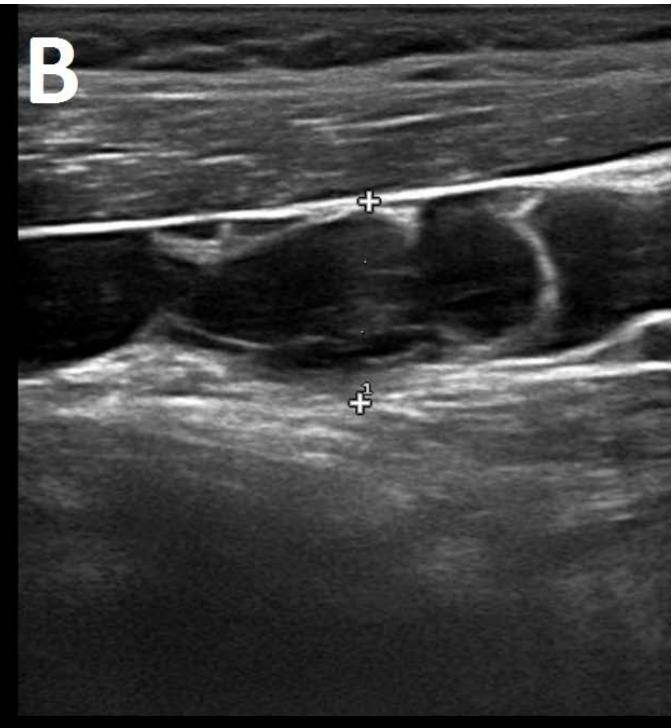

Figure/Patient 1

A 7 year-old girl presenting with a tumefaction at the level of the right latero-cervical region. US scans show a $43 \times 14$ mm subcutaneous fluid formation with septa extending from the root of the neck to the submandibular region (A-B). Doppler-mode demonstrates lack of blood flow within the lesion or the septa (C-D). Diagnosis of cystic lymphangioma is done.